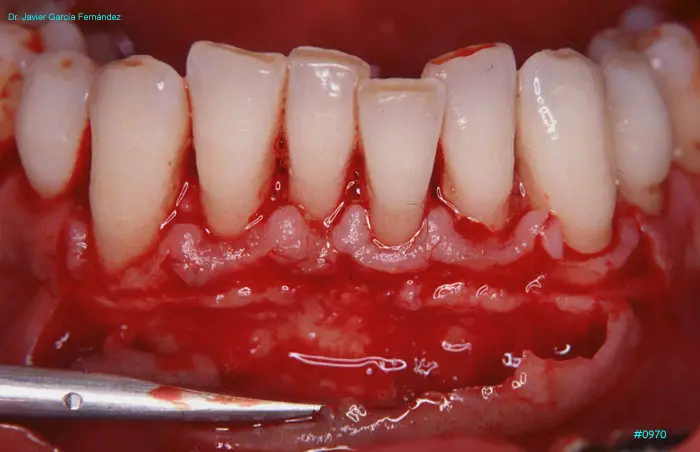

Atlas of Surgical Techniques in Periodontics. Chapter III. Atlas de Técnicas Quirúrgicas en Periodoncia